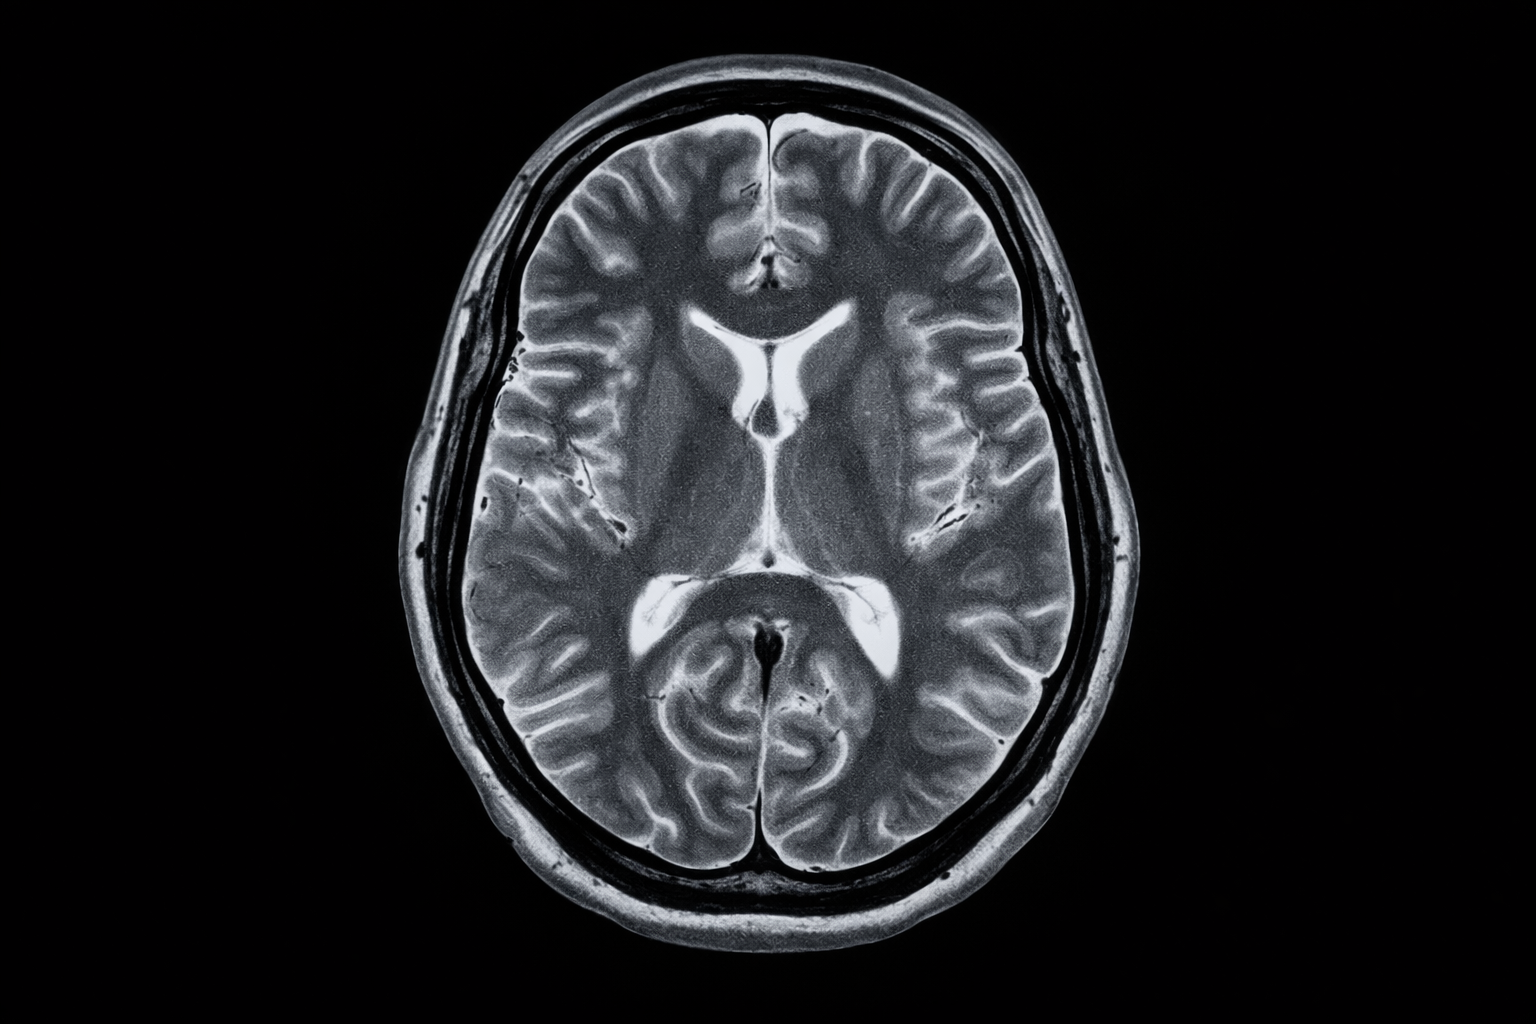

L’IRM (Imagerie par Résonance Magnétique) est une technique d’imagerie médicale qui utilise des champs magnétiques et des ondes radio pour créer des images détaillées de l’intérieur du corps. Contrairement aux rayons X, l’IRM n’utilise pas de radiations ionisantes. Lors d’une IRM, le patient est placé à l’intérieur d’un scanner qui génère un champ magnétique puissant. Les noyaux d’hydrogène présents dans les tissus du corps réagissent à ce champ magnétique en émettant des signaux radio.

Ces signaux sont captés par un scanner, puis traités par un ordinateur pour créer des images détaillées des organes, des tissus et d’autres structures internes du corps. L’IRM est couramment utilisée pour diagnostiquer et évaluer diverses conditions médicales, notamment les lésions cérébrales, les problèmes articulaires, les tumeurs, les troubles vasculaires, et d’autres affections. Elle offre une excellente résolution des tissus mous, ce qui la rend particulièrement utile dans l’exploration du cerveau, des muscles, des ligaments et d’autres structures anatomiques où d’autres techniques d’imagerie peuvent être moins précises.